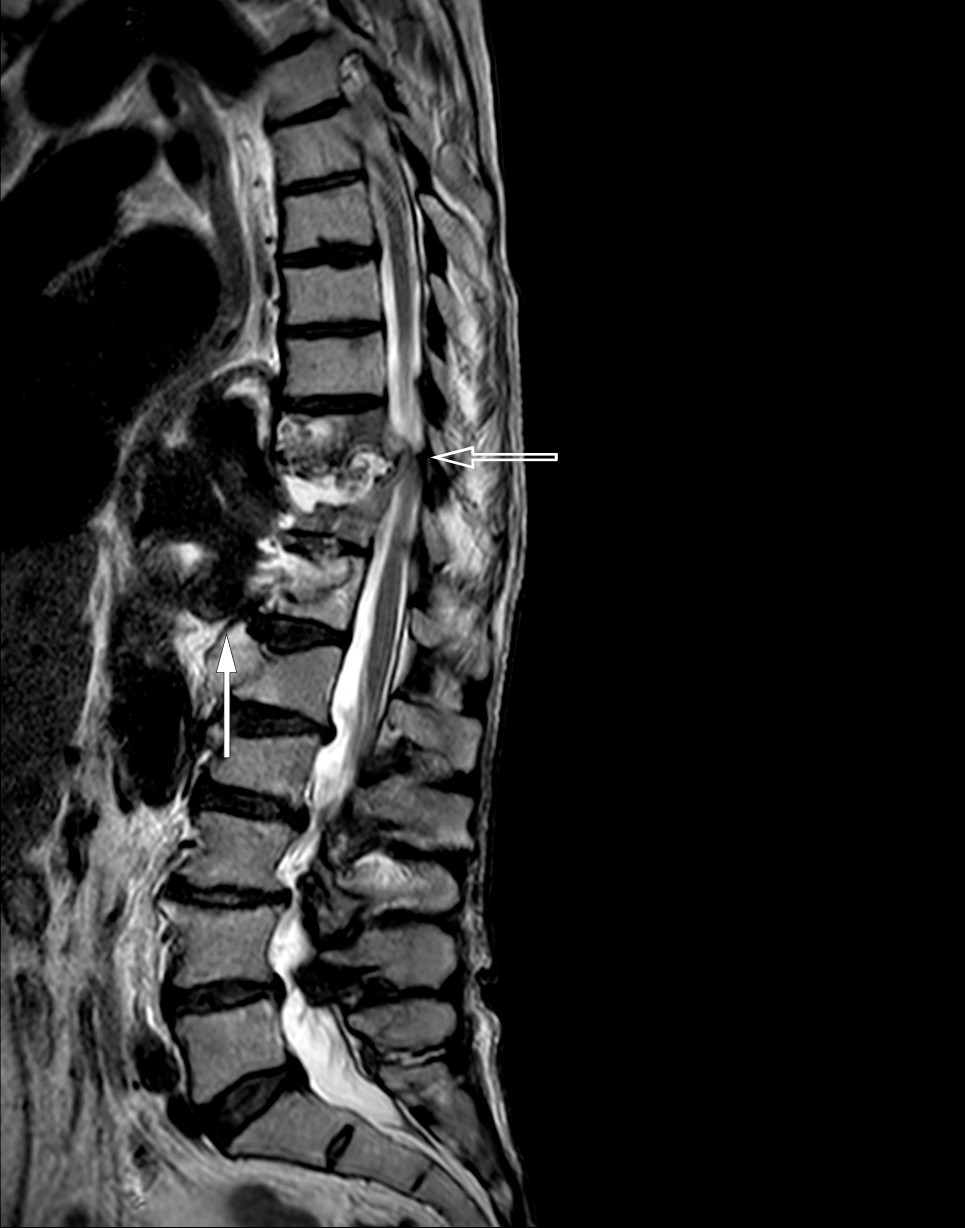

MR-kontroll ble utført to uker etter beinbiopsi og viste lettgradig volumøkning av det mykotiske aneurismet, paraaortale abscesser, spondylodiskitt i Th10/Th11 samt økt mengde pleuravæske (figur 2). Antibiotika hadde ikke hatt noen overbevisende effekt. Situasjonen var uholdbar og svært belastende for pasienten, som på dette tidspunktet var sterkt preget av kakeksi og stort sett var sengeliggende med intraktable ryggsmerter. Tre og en halv måned etter første innleggelse ble hun for tredje gang overført til ny spesialavdeling ved regionssykehuset og operert med stabiliserende ryggkirurgi med fiksasjon av Th7–L3.